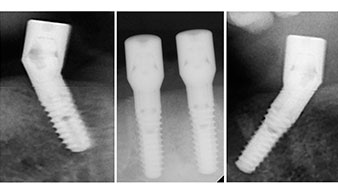

Zur Planung und Risikominimierung wurde eine dreidimensionale Volumentomografie (DVT, Planmeca) erstellt. Dieses zeigte, dass die Qualität und Quantität des Knochens für eine Operation und Sofortversorgung nach der Fast & Fixed-Methode ausreichend war. Nach Protokoll dieses Konzeptes wird in Regio 35, 32, 42 und 45 implantiert. Durch die bis zu 45-Grad-Schiefstellung der distalen Implantate wird das Durchtrittsprofil nach posterior verlegt und ein größeres Stützpolygon erreicht (Abb. 3).

Das chirurgische Protokoll der verwendeten Implantate (SKY, bredent medical) schreibt eine Umdrehungszahl von 1.200/min für die Pilotbohrungen vor (Abb. 7–9).

Dies entspricht der nächsten Position der Voreinstellung am Implantmed. Zu erkennen ist die etwa 45-Grad-Schräghaltung des W&H Winkelstückes nach mesiokaudal in Regio 45, um den Nervus mentalis zu schonen. Das Foramen mentale gilt als anatomische Orientierung für alle Bohrungen in diesem Bereich. Die anschließenden Bohrungen werden mit einer reduzierten Umdrehungszahl von 300/min durchgeführt (Abb. 10 und 11).

Die nächste programmierte Einstellung ist bereits die Implantateinbringung. Die Implantate werden in unserem Hause standardmäßig mit einer Kraft von 32Ncm inseriert (Abb. 12 und 13).

Die absolute Voraussetzung für die Sofortversorgung ist die hohe Primärstabilität. Um diese zu erfüllen, wurde in diesem Fall auf ein Gewindeschneiden verzichtet. Die hier verwendete Antriebseinheit Implantmed von W&H besitzt hierfür einen eigenen Modus, der ebenfalls direkt anwählbar und für viele Indikationen unverzichtbar ist. Die letzten Umdrehungen bei der Implantateinbringung überschritten den Wert von 32Ncm und wurden manuell durchgeführt. Hierfür empfiehlt es sich, die Selbstschneidefunktion der Implantate auszunutzen und das Implantat mehrmals vorwärts und rückwärts zu drehen. So gelangt das Implantat schrittweise näher bis zur endgültigen Position, ohne zu starken Druck auf den Knochen auszuüben (Abb. 14).

Um die Divergenz der distalen Implantate auszugleichen, werden abgewinkelte Abutments (35 Grad) eingeschraubt, sodass die Austrittsprofile sämtlicher Implantate möglichst senkrecht zur Kauebene stehen. Dies ist Voraussetzung, um die provisorische und später auch die endgültige Versorgung okklusal verschrauben zu können (Abb. 15 und 16).